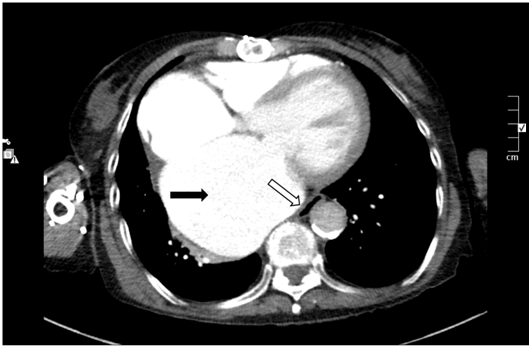

An 84 year-old lady ex-smoker with prior coronary artery bypass graft surgery and mitral/tricuspid valve repair presented with breathlessness, dysphagia and weight loss. An echocardiogram showed cardiomegaly and moderate mitral valve regurgitation. Computed tomography of the thorax (Figure 1) excluded malignancy but confirmed extrinsic oesophageal compression due to gross cardiomegaly.

An 84-year-old lady presented with dysphagia, dyspnoea and weight loss. She had a history of ischaemic and rheumatic heart disease (prior coronary artery bypass graft surgery with mitral and tricuspid valve repair), permanent atrial fibrillation and permanent pacemaker. She was non-compliant with diuretic therapy. Chest radiograph showed pulmonary congestion with gross cardiomegaly. An echocardiogram demonstrated a grossly dilated left atrium (volume 239ml/m2 indexed to body surface area, normal <34ml/m2), dilated left ventricle with severely impaired systolic function and moderate mitral valve regurgitation but no evidence of valvular vegetations. A computed tomography (CT) thorax excluded malignancy but confirmed extrinsic oesophageal compression due to gross cardiomegaly (Figure 1). Conservative management with reinstatement of diuretics and optimisation of anti-heart failure treatment caused resolution of her symptoms.

Figure 1 Computed tomography thorax demonstrating grossly dilated left atrium (black arrow) causing extrinsic compression of the esophagus (white arrow).